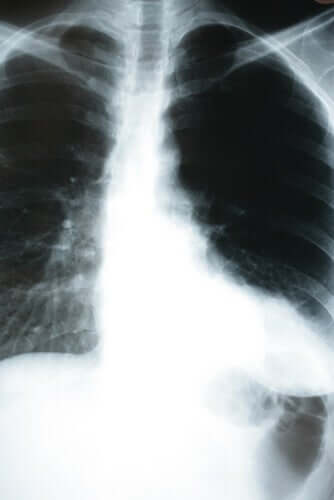

Cependant, dans le cas de la pneumonie silencieuse, c’est le contraire qui se produit. Dans différents hôpitaux de New York et du Brésil, on a observé que de nombreux patients atteints de pneumonie silencieuse semblaient bien portants. On ne découvre la pathologique qu’en mesurant l’oxygène ou en faisant une radiographie du thorax.

Par conséquent, si vous suspectez un coronavirus, il est recommandé de mesurer votre saturation en oxygène et même de faire une radiographie pulmonaire. Surtout s’il s’agit d’une personne qui a contacté une personne infectée ou qui fait partie d’un groupe à risque.